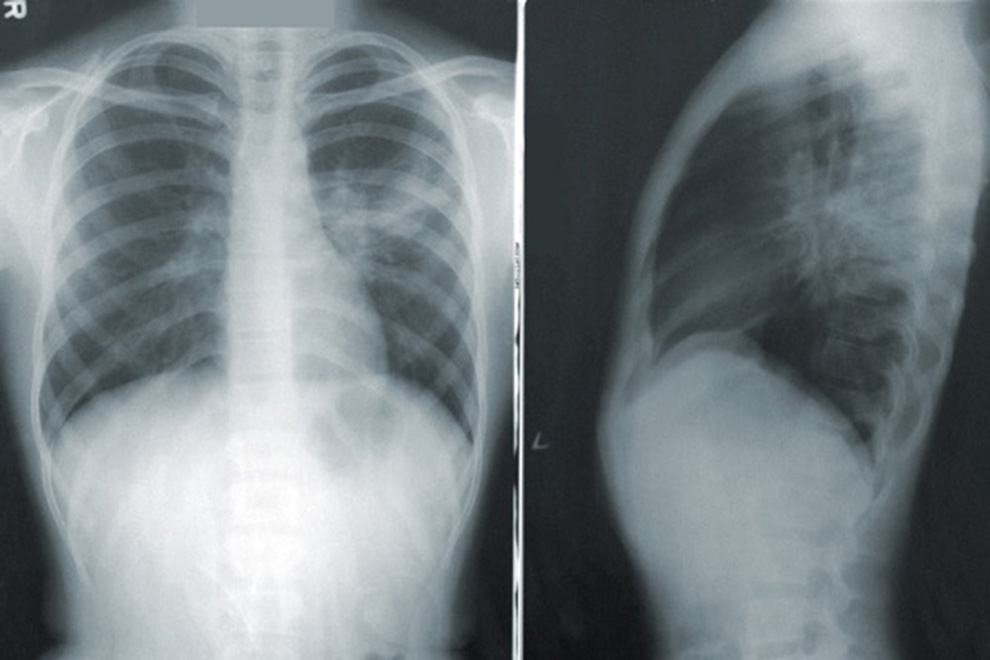

NotiPress.- Ante la llegada de la Covid-19, surgió preocupación por el panorama para pacientes con trastornos respiratorios, como el asma o la enfermedad pulmonar obstructiva crónica (EPOC). Según la Organización mundial de la salud (OMS), en la actualidad hay en el mundo más de dos millones de personas con asma y, en 2016, la prevalencia de la EPOC fue de 251 millones de casos. Para conocer más sobre este tema, NotiPress acudió a un webinar de la empresa de investigación farmacéutica Boehringer Ingelheim y estos fueron los datos más relevantes.

Según el doctor Rafael Hernández Zenteno, neumólogo jefe del servicio de asma y EPOC del Instituto nacional de enfermedades respiratorias (INER), 3.3% de la población padece asma en México. Además señaló, con información del Instituto Nacional de Estadística, Geografía e Informática, que la EPOC y el asma representan la séptima causa de defunción en México. En el mundo, afirmó, la EPOC pasó de ser la sexta causa de muerte, en 1990, a ser la tercera en 2020, de acuerdo a la OMS. En concreto, se refirió a la EPOC como un problema de salud de alta prevalencia, subdiagnosticada y subtratada en etapas tempranas y avanzadas.

En relación con la Covid-19, el doctor Hernández citó un estudio realizado en España donde su ubica a la EPOC como una comorbilidad en menos del 10% de los casos de Covid-19. Mencionó, el escenario es similar para México y que, pese a una tasa de contagios baja en personas con EPOC, los resultados suelen ser severos. También recomendó no suspender los tratamientos de base de las personas con EPOC y asma, pues con esto se ha observado un resultado más benévolo si se contagian. La adherencia al uso correcto del inhalador se relaciona con una redacción de la mortalidad, aunque aún se desconoce la razón de este efecto, señaló.